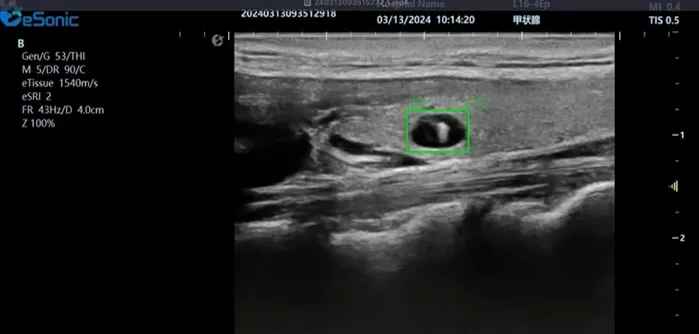

百乐博平台医疗(ESI)表示,其最新的人工智能功能可以帮助到医疗机构的工作效率,功能包括,实时、动态、快速自动识别病灶,良恶性病灶概率预测,甲状腺结节和乳腺的二维灰阶动态自动实时检测需求,提供多个结节动态检测轮廓框。实时获取多幅具备临床特征(大小、属性等)的结节切面,同时提供当前切面所示结节的结节大小、属性特征、TI-RADS 分级。

对于甲状腺结节相关的自动检测功能,甲状腺结节病灶检出率≥95%,良恶性分类灵敏度≥90%、良恶性分类特异度≥85%。